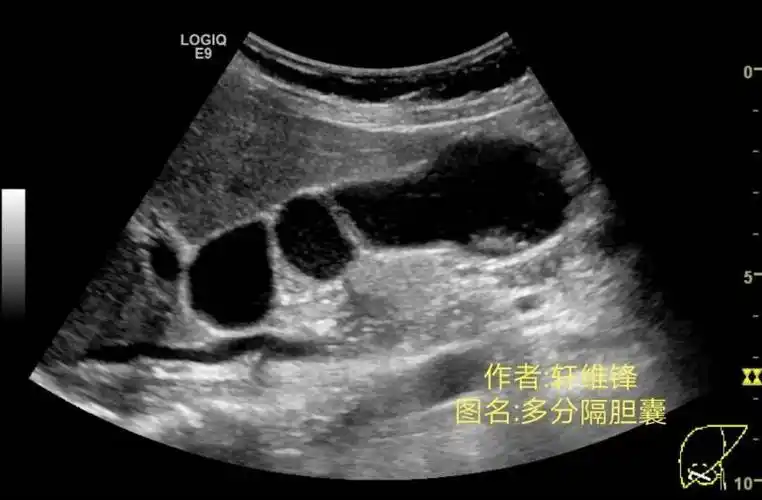

胆囊腺肌症及其它美图分享